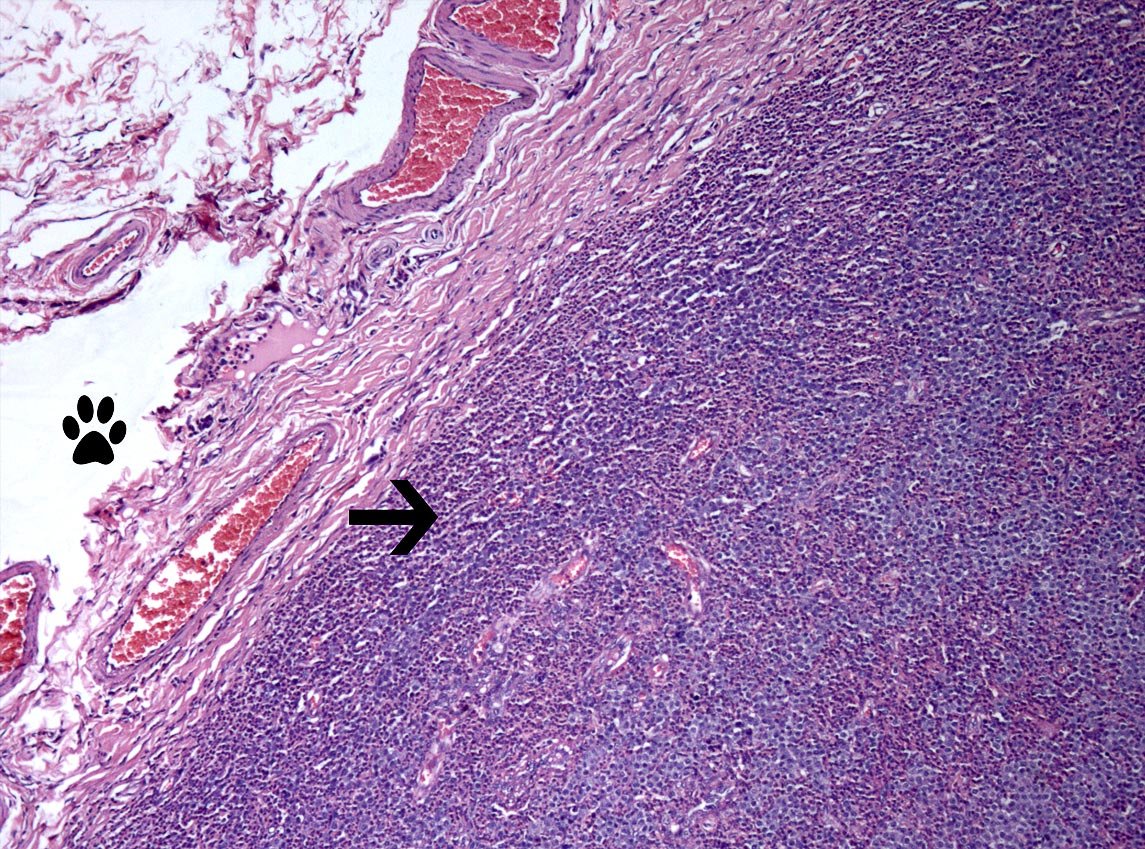

Finalmente. En las dos siguientes figuras(6-A,6-B), se aprecia de forma clara el concepto histopatológico de mastocitoma subcutáneo.

Fig.6-A. Todo lo rosado es dermis( folículos pilosos, etc.). La patita, es el tejido adiposo, la flecha, indica la capsula del tumor.

Fig.6-B. Un mayor acercamiento de la fig.6-A. La flecha indica el crecimiento tumoral.